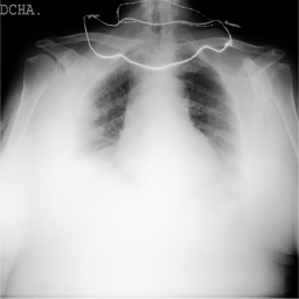

Samples of the dataset are depicted in Figure 3.

Figure 3. An example of an X-ray scan images taken from the dataset (a, b, c) with a label of COVID-19 negative, (d, e, f) COVID-19 positive.